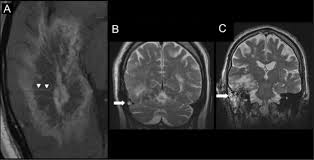

Teaching Neuroimages Brain Mri Aspects Of Isolated Cerebral Mucormycosis Neurology

Teaching Neuroimages Brain Mri Aspects Of Isolated Cerebral Mucormycosis Neurology from n.neurology.org